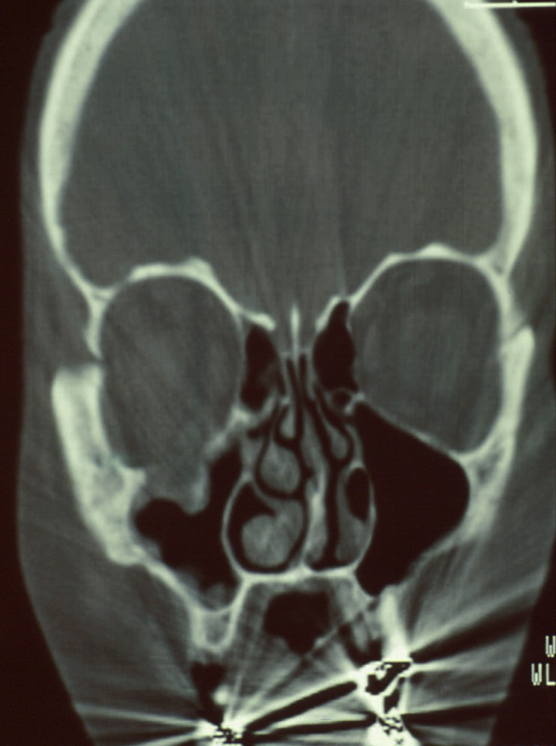

What part of the orbit has been compromised here?

What injury causes this to happen?

What type of trauma causes this injury?

Inferior wall of the orbit

Orbital blow out fractures

Blunt trauma

A certain muscle commonly gets tethered in orbital blow out fractures. What muscle is this?

Inferior Rectus